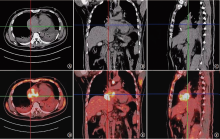

原发性心脏血管肉瘤是一种来源于血管内皮的恶性肿瘤,极为罕见且预后极差,病理诊断特异性及敏感性较高的标志物是CD31和CD34,手术不能根治性切除,姑息放疗、系统化疗和抗血管生成靶向治疗可延长患者生存期。现报道1例心脏原发血管肉瘤患者的诊疗经过,并就相关文献进行复习,以提高对该类疾病的认识。